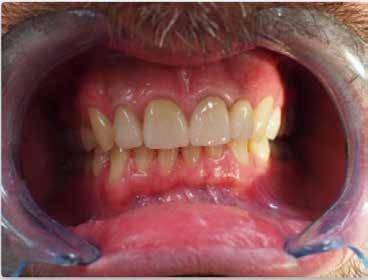

A 28 éves hölgypáciens is elsősorban a szép mosoly elérésének igénye miatt szeretett volna fogszabályozást, bár tudomása volt a mélyharapásáról (1–5. képek).

A kezelési célokat a fogívek tágítása a megfelelő mosolyszélességhez és az alsó frontfogak torlódásának feloldásához, valamint a mélyharapás és a kismértékű disztálharapás korrekciója jelentették (6–11. képek).

Passzív önligírozó fix fogszabá-

lyozó készülékkel 15 hónapig tartott a kezelése. Az ilyen mélyharapásos esetekben nagyon fontos, hogy a harapásemelésnél nem történik intrúzió a felső fogíven, mert az kifejezetten negatívan befolyásolná a vertikális mosoly-display-t! A fogszabályozó kezelés után, ahogy az általában lenni szokott, a bölcsességfogak eltávolításra kerültek. Mint minden esetben, a fogszabályozás aktív fázisa után a retenció, a passzív helyben tartó fázis a kezelési eredmény megtartásához rendkívül fontos!